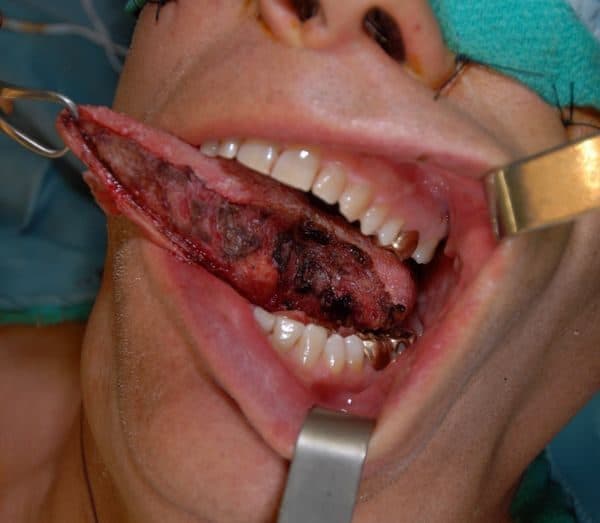

Ung thư lưỡi là bệnh ung thư phổ biến nhất ở vùng họng miệng và thường gặp nhất là ung thư phần lưỡi phần di động là phần liên quan đến sàn miệng. Ung thư lưỡi có thể gặp ở nhiều độ tuổi khác nhau nhưng phổ biến hơn cả ở nam giới trên 50 tuổi.

Ung thư lưỡi sống được bao lâu

Ung thư lưỡi sống được bao lâu? Cũng giống như tất cả các bệnh ung thư khác, thời gian sống cho bệnh nhân ung thư lưỡi phụ thuộc vào rất nhiều yếu tố bao gồm: giai đoạn tiến triển ung thư, lựa chọn phương pháp điều trị, độ tuổi, thể trạng bệnh nhân…